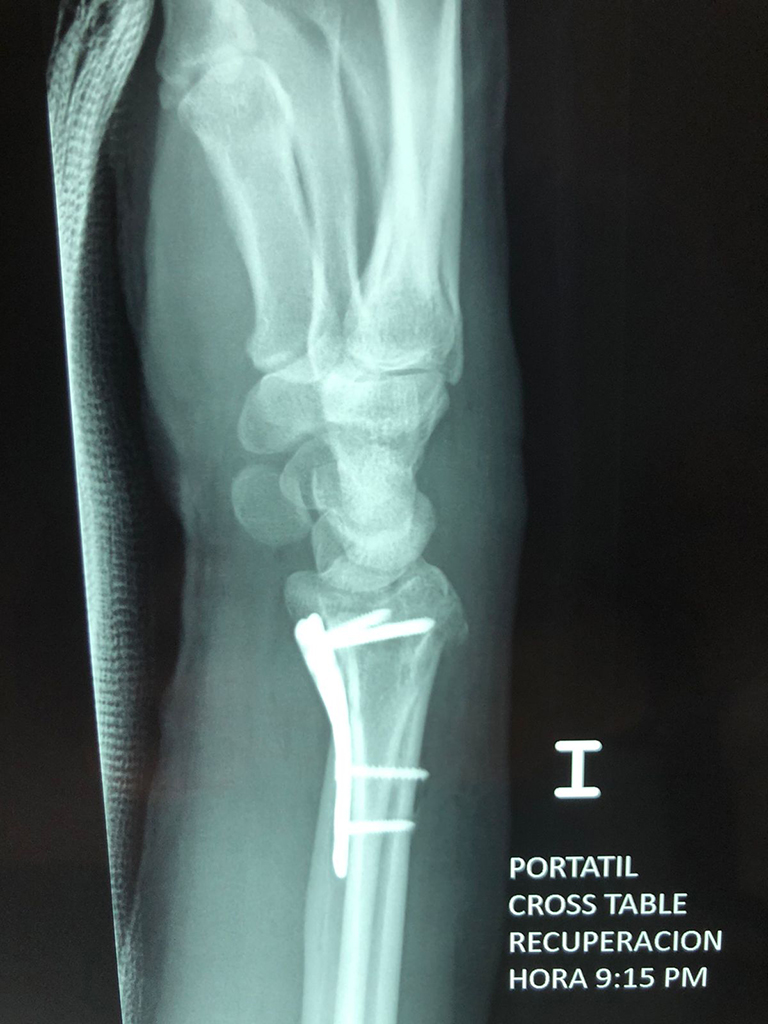

Cirugía de Muñeca y Mano

Los procedimientos más comunes en cirugía de la mano son aquellos destinados a reparar traumatismos, incluyendo lesiones de tendones, nervios, vasos sanguíneos, y articulaciones; huesos fracturados; y quemaduras, cortes, y otros daños de la piel.